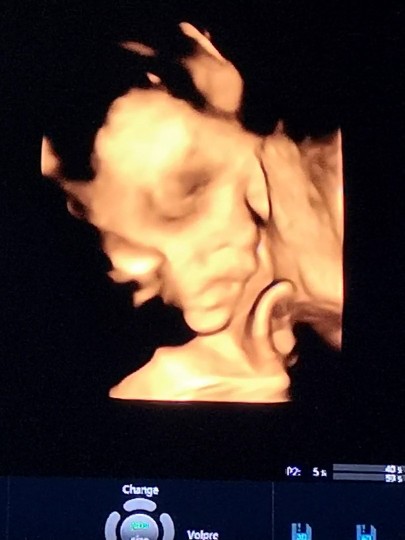

อัลตราซาวด์ 4 มิติ

มีแม่ๆคนไหน ซาวด์ 4 มิติบ้างไหมค่ะ ราคาประมาณเท่าไหร่กัน ถ้าน้องอยู่ท่าตามภาพที่โพส จะเห็นหน้าน้องไหมค่ะ 32 วีคค่ะ อยากเห็นหน้าลูก แต่หันตูดให้อย่างเดียวเลยค่ะ ?